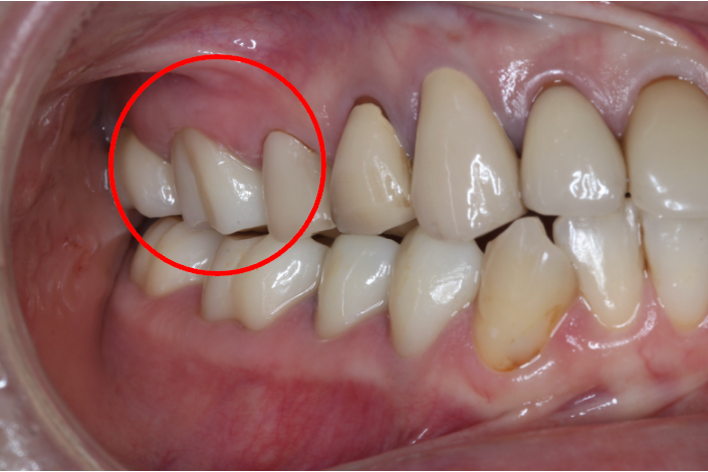

セラミック症例④

年齢50代男性

治療期間1ヶ月

治療内容セラミックインレー、クラウン

治療箇所

左下7番 左上4番、5番、7番 右下6番 右上5番

治療費用600,000円